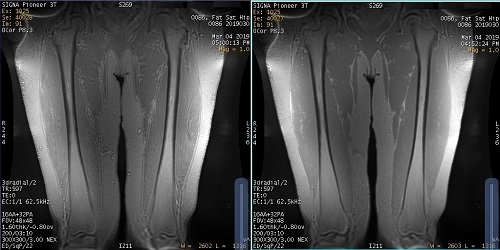

Figure 2. Example of Chemical Shift Reduction off and on with extremity scan

Table 2. Image legend

NumberDescription

LeftChemical Shift Reduction turned off.

RightChemical Shift Reduction turned on. Note the reduced chemical shift artifact.

• For fat and water mixed anatomies such as the neck and extremities, turning on Chemical Shift Reduction can dramatically reduce the ghosting artifact.

• Recommended for use with musculoskeletal scans and not for brain scans.